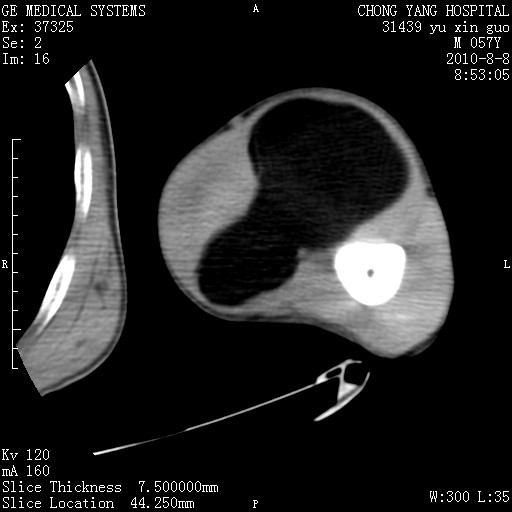

标题: CT28267:M57Y 上臂包块8年余。 [打印本页]

标题: CT28267:M57Y 上臂包块8年余。

上臂软组织内脂肪瘤。

包膜光滑、完整的脂肪密度肿块,支持脂肪瘤。